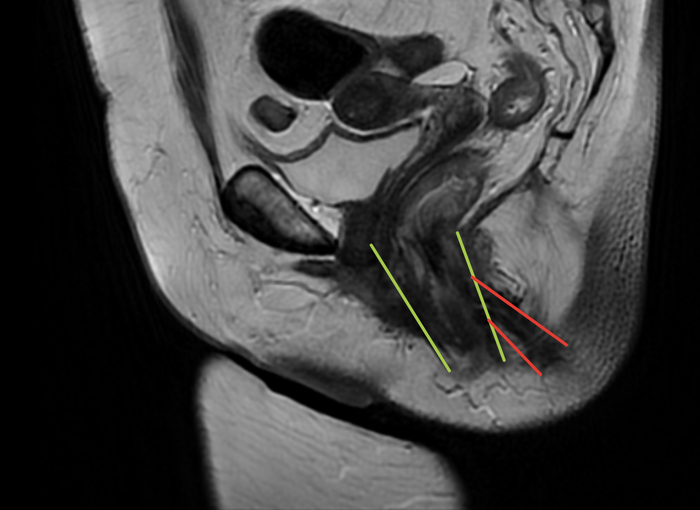

Лучевые диагносты выполнили работу на отлично, но радости от этого не было. Свищ. Толстенный. Уже отжирает половину сфинктерного комплекса, вызывает недержание газов и периодически жидкой фракции.